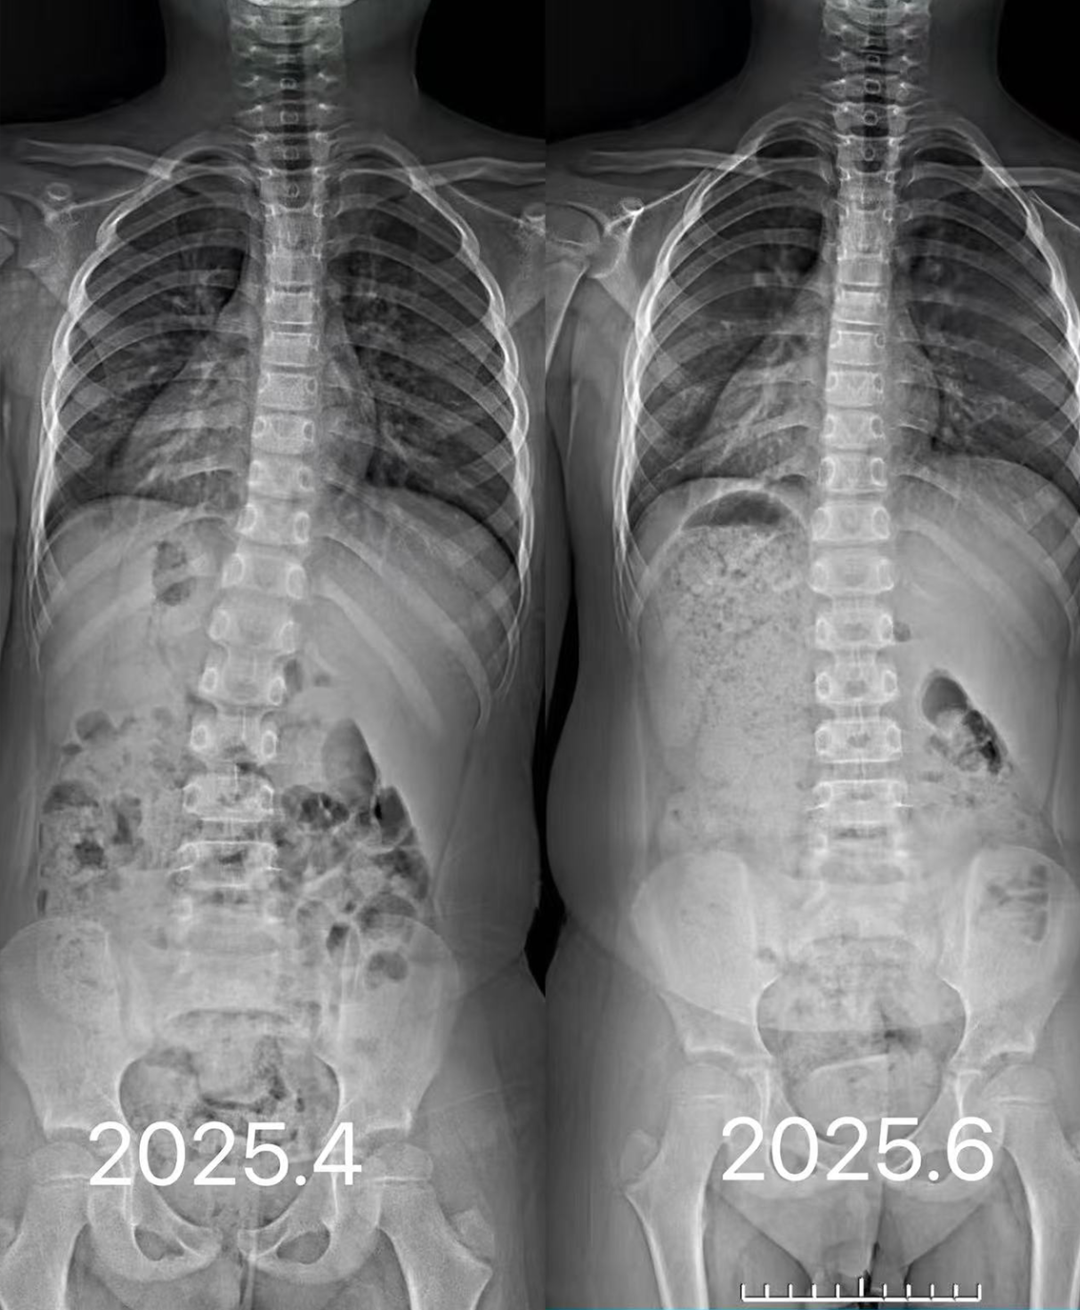

专业诊断:专家解读全脊柱X光片 + 步态生物力学分析